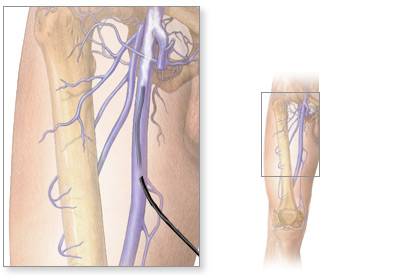

Для выполнения флебографии вен нижних конечностей пациент направляется в рентгенологическое отделение. Перед введением контраста пациент укладывается на стол, после чего врач определяет подкожную вену голени или стопы, в которую будет введен препарат. Для этого выполняется прокол вены (венепункция) или небольшой ее надрез под местной анестезией (венесекция). Далее катетером вводится около 20 мл одного из применяемых в данной клинике препаратов – омнипака, ультрависта и др. При необходимости на исследуемую конечность накладывается жгут для лучшего распространения вещества по венозной системе конечности. После серии рентгеновских снимков жгут снимается, в вену пациенту вводится небольшое количество физ. раствора, а пациент ожидает результата обследования.

пример нацеленного введения рентеноконтрастного вещества

Длительность процедуры составляет от 30-40 минут до часа, не вызывая в целом у пациента болезненных ощущений. Тем не менее, у части пациентов может отмечаться боль при проколе вены, а также легкая тошнота и головокружение после введения контраста.